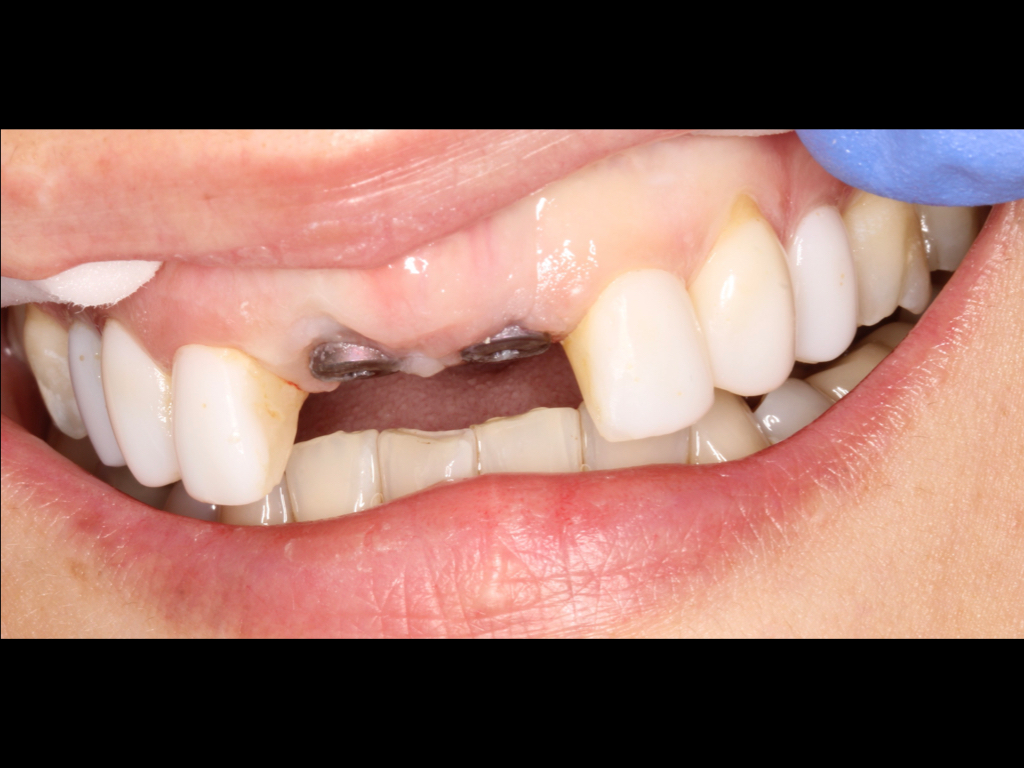

Failing Dental Bridge Being Replaced by Dental Implants